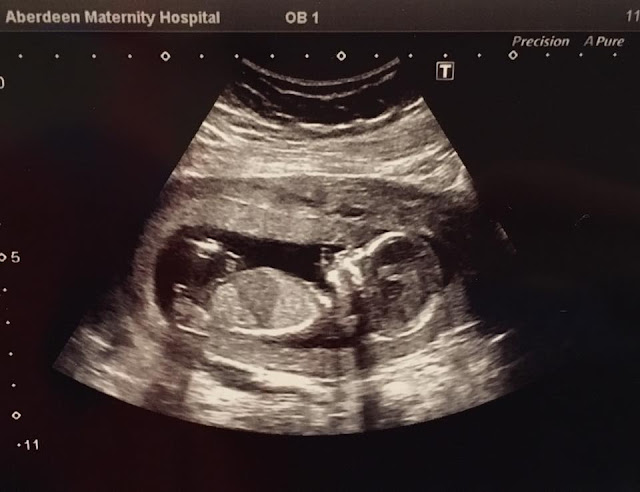

Guys...this time...it isn't just a food baby!

Yes, I'm pregnant, I've quite recently crossed over into my second trimester, which means our baby will be due to arrive on (well around) the 25th of July 2017 (fashionably late like their Mum I'm sure or you know...just busy sleeping like their Dad)